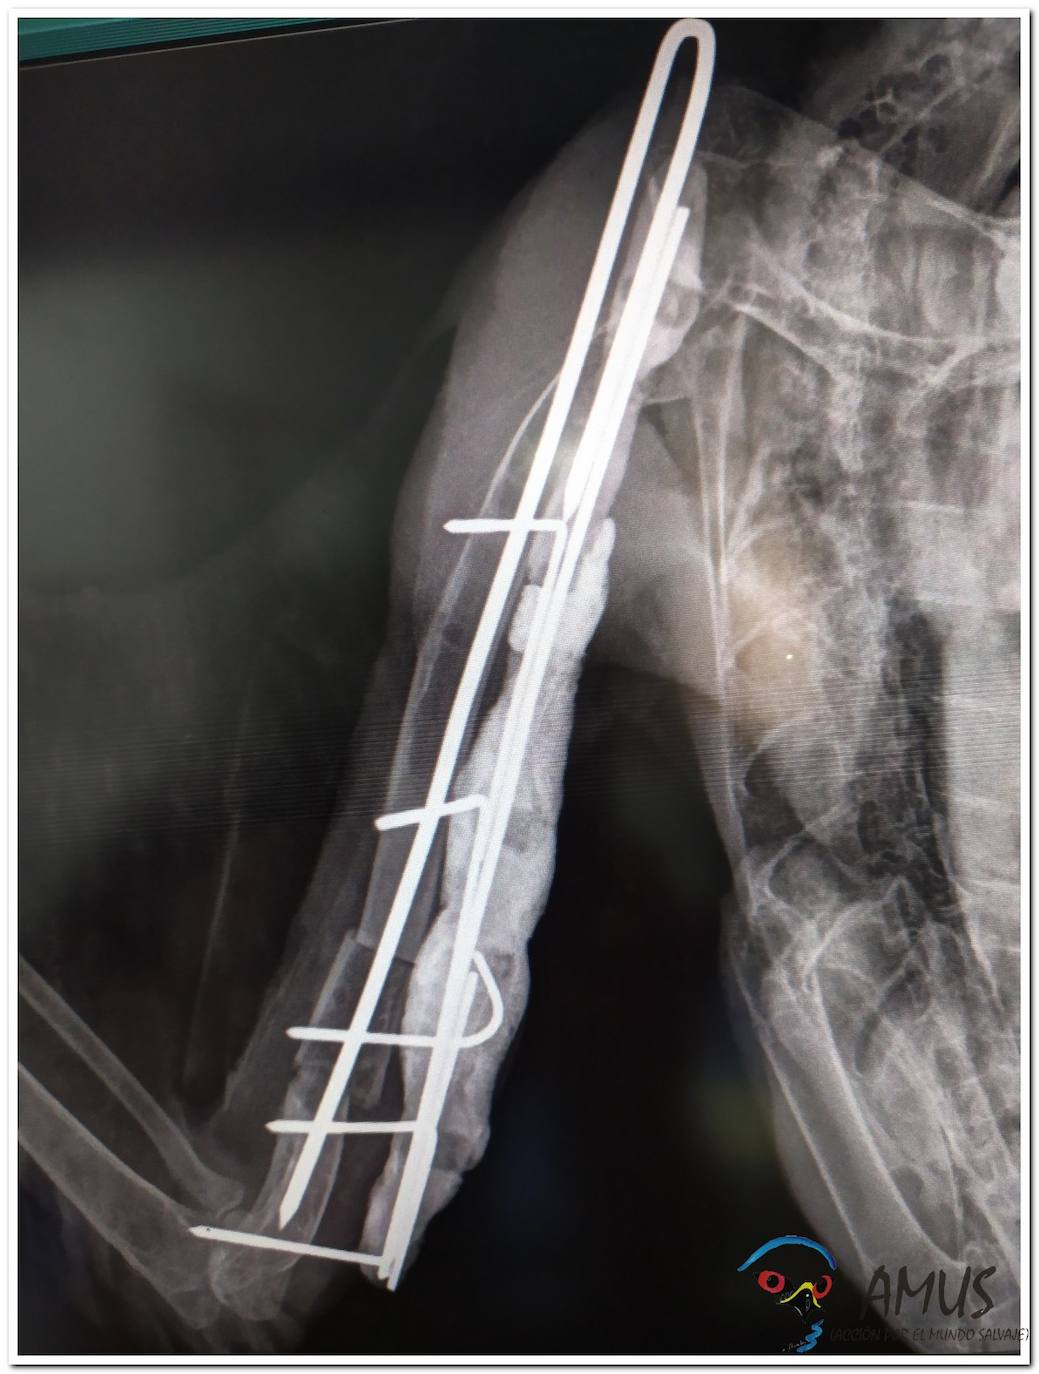

Amus interviene quirúrguicamente a un Milano real

Ave catalogada «en peligro de extinción»

Operacion del Milano real